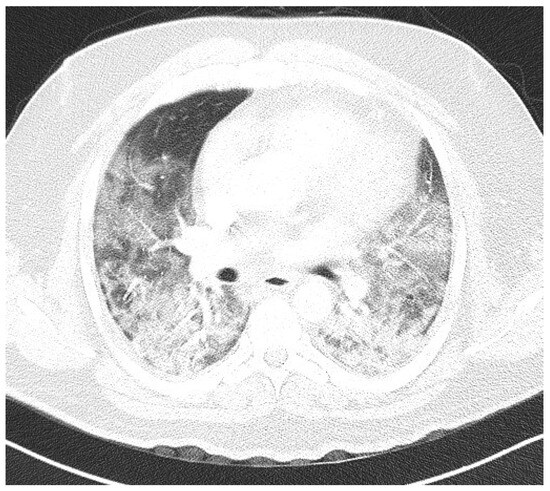

Laboratory findings were mostly normal; C-reactive protein was elevated in all patients with a mean value of 129.7 ± 80.74 mg/L. The arterial blood gas analysis showed hypoxemic respiratory failure. Chest X-rays in all patients showed bilateral inhomogeneous infiltrates (Figure 1 and Figure 2). In three patients, CTPA was performed, which ruled out pulmonary thromboembolism, but ground-glass opacifications with consolidation of the lung parenchyma were described in all of them (Figure 3 and Figure 4) [15].

Figure 3. CTPA upon admittance: patient 1. Bilateral ground glass opacifications (severity score: 15–25; chest CT severity score: 14) typical for COVID-19 pneumonia.